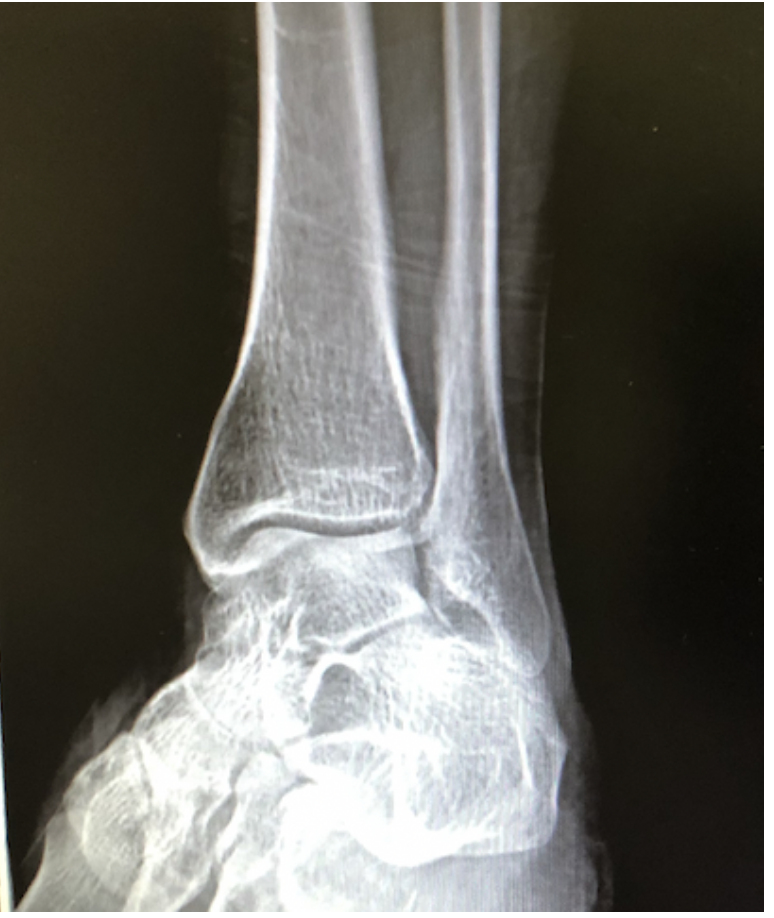

14

Q

What view is this?

A

Ankle AP